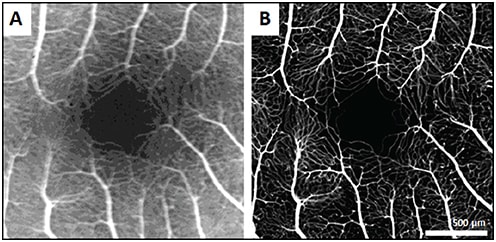

Due to its high magnification, confocality, and resolution, AOSLO can visualize the retinal microvasculature with unprecedented detail, but it is often hampered by lack of contrast. Oral fluorescein administration, coupled with confocal AOSLO (AOSLO FA), enhances the contrast of perfusion maps, enabling the detection of even the finest blood vessels, with image quality far superior to conventional intravenous fluorescein angiography (Figure 6).8

Figure 6. Comparison of IVFA image (A) and AOSLO FA image (B) of fovea in a healthy control.8

COURTESY OF OSA PUBLISHING